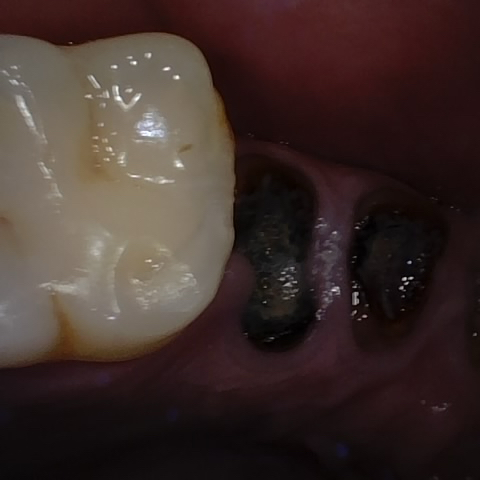

Annotated as "Good"

Original Image Rendering Image